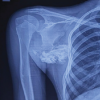

It was not associated with pain. There was no history of trauma to left shoulder. On examination, a hard and trans-illumination negative swelling, measuring 6*4*3 cm, was noted on the lateral aspect of left shoulder just below acromion process (Fig. 1). The swelling was non-mobile, non-tender, and non-adherent to overlying skin or muscle tissue. Skin over the swelling appeared normal. X-ray of the left shoulder showed irregularly ossified lesion on the lateral aspect of proximal humerus just below acromion process (Fig. 2) MRI was done and revealed a large, well defined, fairly well capsulated, and lobulated mass along lateral aspect of proximal humerus measuring 6*4*3.5 cm in size with a thin stalk connecting to postero-lateral corner of acromion process (Fig. 3). It showed multiple areas of extensive calcification with a very thin cartilaginous cap. Above said features defined a benign lesion but few peculiar signs of Exostoses. Hence, patient was posted for J needle biopsy which suggested bony trabeculae along with thin cartilage without dysplasia. As the lesion was benign, excisional biopsy was planned by direct lateral approach to proximal humerus and the mass was carefully separated from surrounding tissue with blunt dissection (Fig. 4).